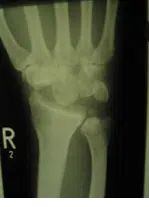

Der Gelenkverschleiß des Handgelenkes hat seine Ursache entweder in fehlverheilten Brüchen vor allem der Speiche oder des Kahnbeins, in Bandverletzungen der Handwurzel, einer rheumatischen Erkrankung oder Durchblutungsstörung einzelner Handwurzelknochen, die dann zum Absterben dieser führen kann. (z.B.: Morbus Kienböck).

Häufig sind zur langfristigen Schmerzverbesserung nur teilversteifende Operationen, oder aber die Entfernung einzelner Handwurzelknochen sinnvoll. Nach derartigen Operationen ist die Gesamtbeweglichkeit des Handgelenkes zwar reduziert – mit 30° Streckung und 30° Beugung- dies ist jedoch im Alltag meist ausreichend und das bei einer deutlichen Reduktion der vormalig vorhandenen Schmerzen.